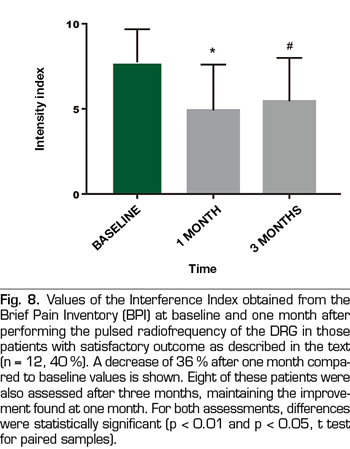

Ten out of these 12 patients showed a variation of three points or more in VNS (more than 50% variation), whereas only 2 patients had a variation of two points on the scale (30% variation). In this group of patients, the Intensity and Interference Indexes were reduced by 47% and 36%, respectively, from 7.4 ± 1.3 to 3.9 ± 1.5 (p <0.0001) for the Intensity Index and from 7.7 ± 1.9 to 4.9 ± 2.7 (p = 0.002) for the Interference Index (Table II, Figures 7 and 8). The 30 patients included reported an average of subjective improvement of 59%. No complications of the procedures were recorded in these cases.

In eight patients with a satisfactory outcome after one month, a three-month evaluation of the procedures was conducted. In these, the VNS remained at low values, 3.8 ± 3.3 (p = 0.007), something similar happened with the Intensity and Interference Indexes, being 4.3 ± 1.6 and 5.4 ± 2.5, respectively (p = 0.001 and p = 0.02, when compared with the baseline values (Figures 6, 7 and 8).